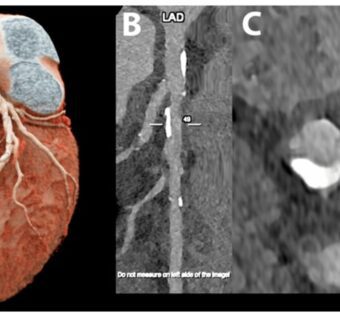

Refining Coronary Artery Disease Assessment with Photon-Counting CTDistilINFO Hospital IT - (Friday February 23, 2024) - Daily Reads/ DistilINFO Hospital IT | |

![]() | The utilization of Ultrahigh-Resolution Photon-Counting CT (PCD-CT) marks a significant breakthrough in the assessment of Coronary Artery Disease (CAD). Published in Radiology, a study demonstrates its superiority over conventional methods, particularly in cases with... #PhotonCountingCTTechnology: Photon-counting CT technology is revolutionizing coronary artery disease assessment by providing higher resolution images and reducing radiation exposure.#AdvantagesofPhotonCountingCT: This blog post highlights the advantages of using photon-counting CT technology for coronary artery disease assessment, including improved image quality, better tissue differentiation, and reduced artifacts.#ClinicalApplications: Photon-counting CT technology has various clinical applications in the assessment of coronary artery disease, such as detecting calcified and non-calcified plaques, evaluating stenosis severity, and assessing plaque composition.#ComparisonwithConventionalCT: The blog post compares photon-counting CT technology with conventional CT imaging techniques, emphasizing the superior image quality, reduced radiation dose, and increased diagnostic As a healthcare IT expert, write a 50-80 extractive summarization summary for social media platforms, that is focused, accurate, and strictly reflects the content based on a blog post from the given URL. The summary should include all headings from the blog post, with inline hashtags for each heading. When including the inline hashtags, use specific hashtags related to the headings rather than generic healthcare or technology hashtags. If the headings in the blog post are too long or unclear, feel free to rephrase them into shorter, clearer versions that still convey the main idea. The target audience is other healthcare IT professionals.Following is the title and url. Refining Coronary Artery Disease Assessment with Photon-Counting CT https://distilinfo.com/hospitalit/2024/02/23/refining-coronary-artery-disease-assessment-with-photon-counting-ct/ { "id": "chatcmpl-8vSt7d9FShcQIMRSoxEKSm948G4C9", "object": "chat.completion", "created": 1708706433, "model": "gpt-3.5-turbo-0125", "choices": [ { "index": 0, "message": { "role": "assistant", "content": "#PhotonCountingCTTechnology: Photon-counting CT technology is revolutionizing coronary artery disease assessment by providing higher resolution images and reducing radiation exposure.nn#AdvantagesofPhotonCountingCT: This blog post highlights the advantages of using photon-counting CT technology for coronary artery disease assessment, including improved image quality, better tissue differentiation, and reduced artifacts.nn#ClinicalApplications: Photon-counting CT technology has various clinical applications in the assessment of coronary artery disease, such as detecting calcified and non-calcified plaques, evaluating stenosis severity, and assessing plaque composition.nn#ComparisonwithConventionalCT: The blog post compares photon-counting CT technology with conventional CT imaging techniques, emphasizing the superior image quality, reduced radiation dose, and increased diagnostic" }, "logprobs": null, "finish_reason": "length" } ], "usage": { "prompt_tokens": 187, "completion_tokens": 150, "total_tokens": 337 }, "system_fingerprint": "fp_cbdb91ce3f" } Prompt Tokens - 187 |